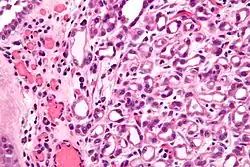

| Micrograph of a nephrogenic adenoma. H&E stain. | |

Nephrogenic adenomas are diagnosed under the microscope by pathologists. Microscopically the tumor shows closely packed small tubular structures in edematous stroma. The tubules show considerable variation in size and shape resembling convoluted tubules of the kidney. The single layer of cells lining the tubules are cuboidal with a scant to moderate amount of cytoplasm. In some areas they may have a hobnail appearance. [2]